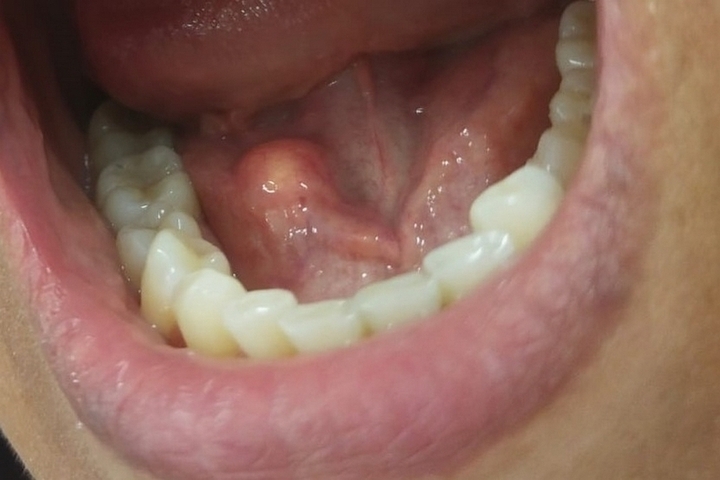

В рамках этого проекта 48-летняя жительница Чебоксар обратилась с жалобами на припухлость под нижней челюстью и боль, возникавшую во время еды.

Осмотр провела заведующий отделением терапевтической стоматологии Оксана Новошинова. Специалист выявила увеличение поднижнечелюстной слюнной железы и уплотнение в области её выводного протока. Пациентку в срочном порядке направили к стоматологу-хирургу Ранилу Камальдинову. Врач поставил диагноз: закупорка протока слюнной железы камнем.

Образовавшийся конкремент был успешно удалён в день обращения женщины за помощью. Благодаря оперативному вмешательству функция слюнной железы полностью восстановилась, что позволило пациентке вернуться к нормальной жизни.